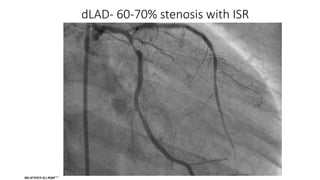

dLAD- 60-70% stenosis with ISR